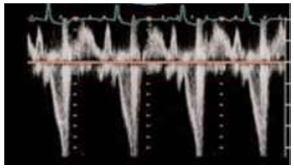

A curva de fluxo abaixo de um doente internado em setor de emergência, sob ventilação mecânica, mostra um fenômeno comum em certos tipos de doente:

As opções a seguir apresentam estratégias válidas para amenizar o fenômeno apontado pela seta, supondo o doente em ventilação a pressão controlada, à exceção de uma. Assinale-a.

Paciente com diagnóstico de Síndrome de Takotsubo clássica, após hemorragia subaracnoide não aneurismática. O ecocardiograma transtorácico realizado à beira leito mostrou acinesia apical e base hiperdinâmica em ventrículo esquerdo. Paciente evoluiu com choque e necessidade de internação em UTI, sendo iniciado dobutamina, por suspeita de choque cardiogênico. Em seguida, há posterior piora do choque, sendo necessário associar altas doses de noradrenalina. Atualmente, está com dobutamina 20mcg/kg/min e noradrenalina 1mcg/kg/min. O exame de Doppler da via de saída do ventrículo esquerdo no ecocardiograma mostra o seguinte padrão, com VTI de 40cm.

A conduta mais adequada no momento é